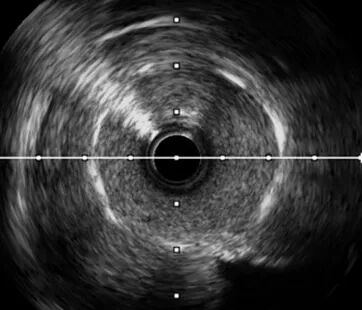

LAD开口不明确,送入IVUS至D1手动回撤,实时寻找LAD开口方向

IVUS回撤过程中可借助血管直径的变化判断闭塞段入口位置,在主支和分支血管汇合段,主支血管管腔在影像下会显示为突然扩张,附近多半可以发现IVUS图像在某个方向上有闭塞主支血管的影像。

复查IVUS可见:LAD多处环形钙化,原支架贴壁不良,支架远端导丝走形在支架外,IVUS指导下重新调整导丝进入支架